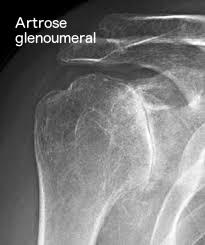

O diagnóstico dessa afecção é realizado através de uma história clínica e exame físico bem feitos. Uma radiografia simples geralmente é suficiente para confirmar o diagnóstico. A tomografia computadorizada pode ser solicitada para melhor avaliação do desgaste ósseo, para um planejamento terapêutico mais adequado. A ressonância magnética, embora não seja necessária para confirmar o diagnóstico, pode ser muito importante para avaliar a qualidade do manguito rotador. Essa avaliação, em muitos casos, também é essencial para se definir o melhor tratamento, principalmente na escolha do tipo de prótese que será usada caso esse seja o tratamento escolhido.